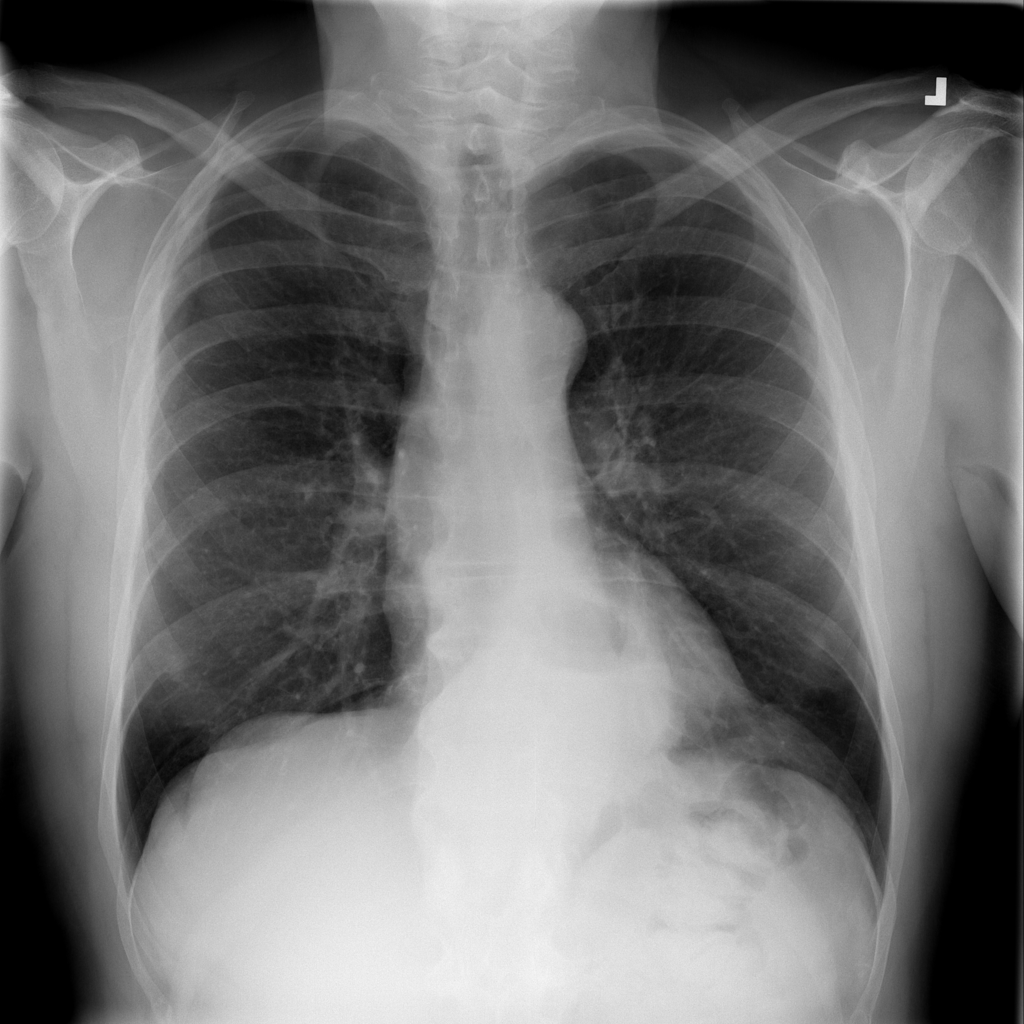

Showing up to 90 reference images for Hernia.

PAT-C048 · IMG-001Hernia

PAT-C048 · IMG-001

PA